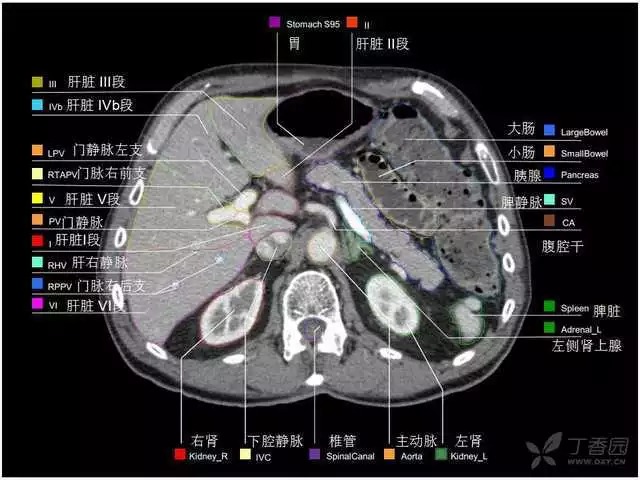

腹部肝脏高清CT断层的图谱

全腹部高清CT图谱,淋巴结彩色图谱,血管解剖图谱大汇总!

超声肝脏分叶及分段

肝脏分段和基本解剖学标志